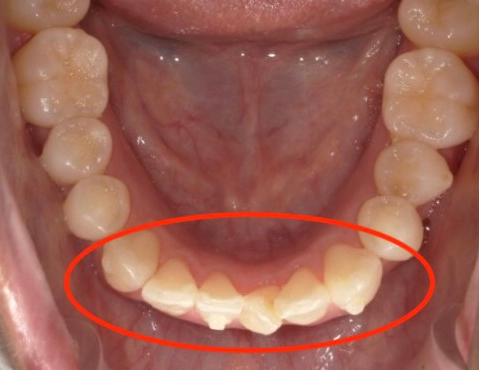

口元が突き出る「口ゴボ」 “口呼吸”が顔立ちを変えてしまう? 放置NGの“リスク”を歯科医師が解説